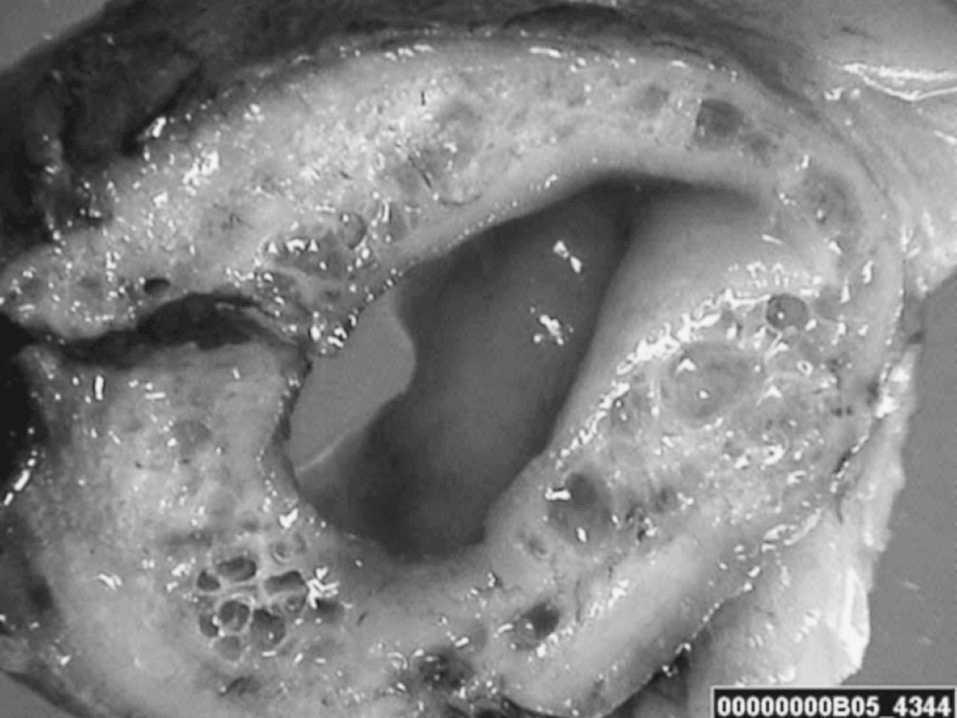

Varón de 97 años, con antecedentes de insuficiencia cardíaca y fibrilación auricular, intervenido de adenocarcinoma de sigma hacía 15 años y colecistectomizado, que consultó por dolor difuso y distensión abdominal de 4 días de evolución sin claro peritonismo. La tomografía computarizada con contraste evidenció neumatosis intestinal con disección aérea de la raíz del mesenterio (fig. 1), neumoperitoneo y trombosis mural de la arteria mesentérica superior. Ante la sospecha de isquemia mesentérica con perforación de víscera hueca, se le sometió a una laparotomía exploradora de urgencia, que objetivó neumatosis intestinal (fig. 2), sin evidenciar perforación del asa. Se realizó una resección de 50 cm del intestino afectado y una anastomosis terminoterminal. El postoperatorio cursó sin complicaciones.

Fig. 2.

Diagnóstico: Neumatosis intestinal idiopática.